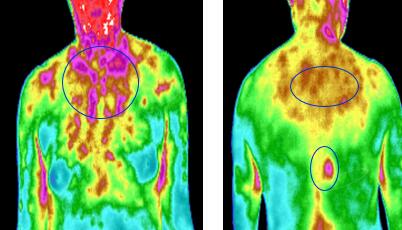

热成像扫描仪通过对非接触探测到的红外热能加以量化,测量温度,通过对其分析。而人细胞代谢过程会产生代谢热,通常情况下,这个变化是一个稳定状态,一旦出现病变,这个稳定状态会被破坏,全维度热成像扫描,评估医师能够观察这种微小的温度变化,找出哪里有健康问题。